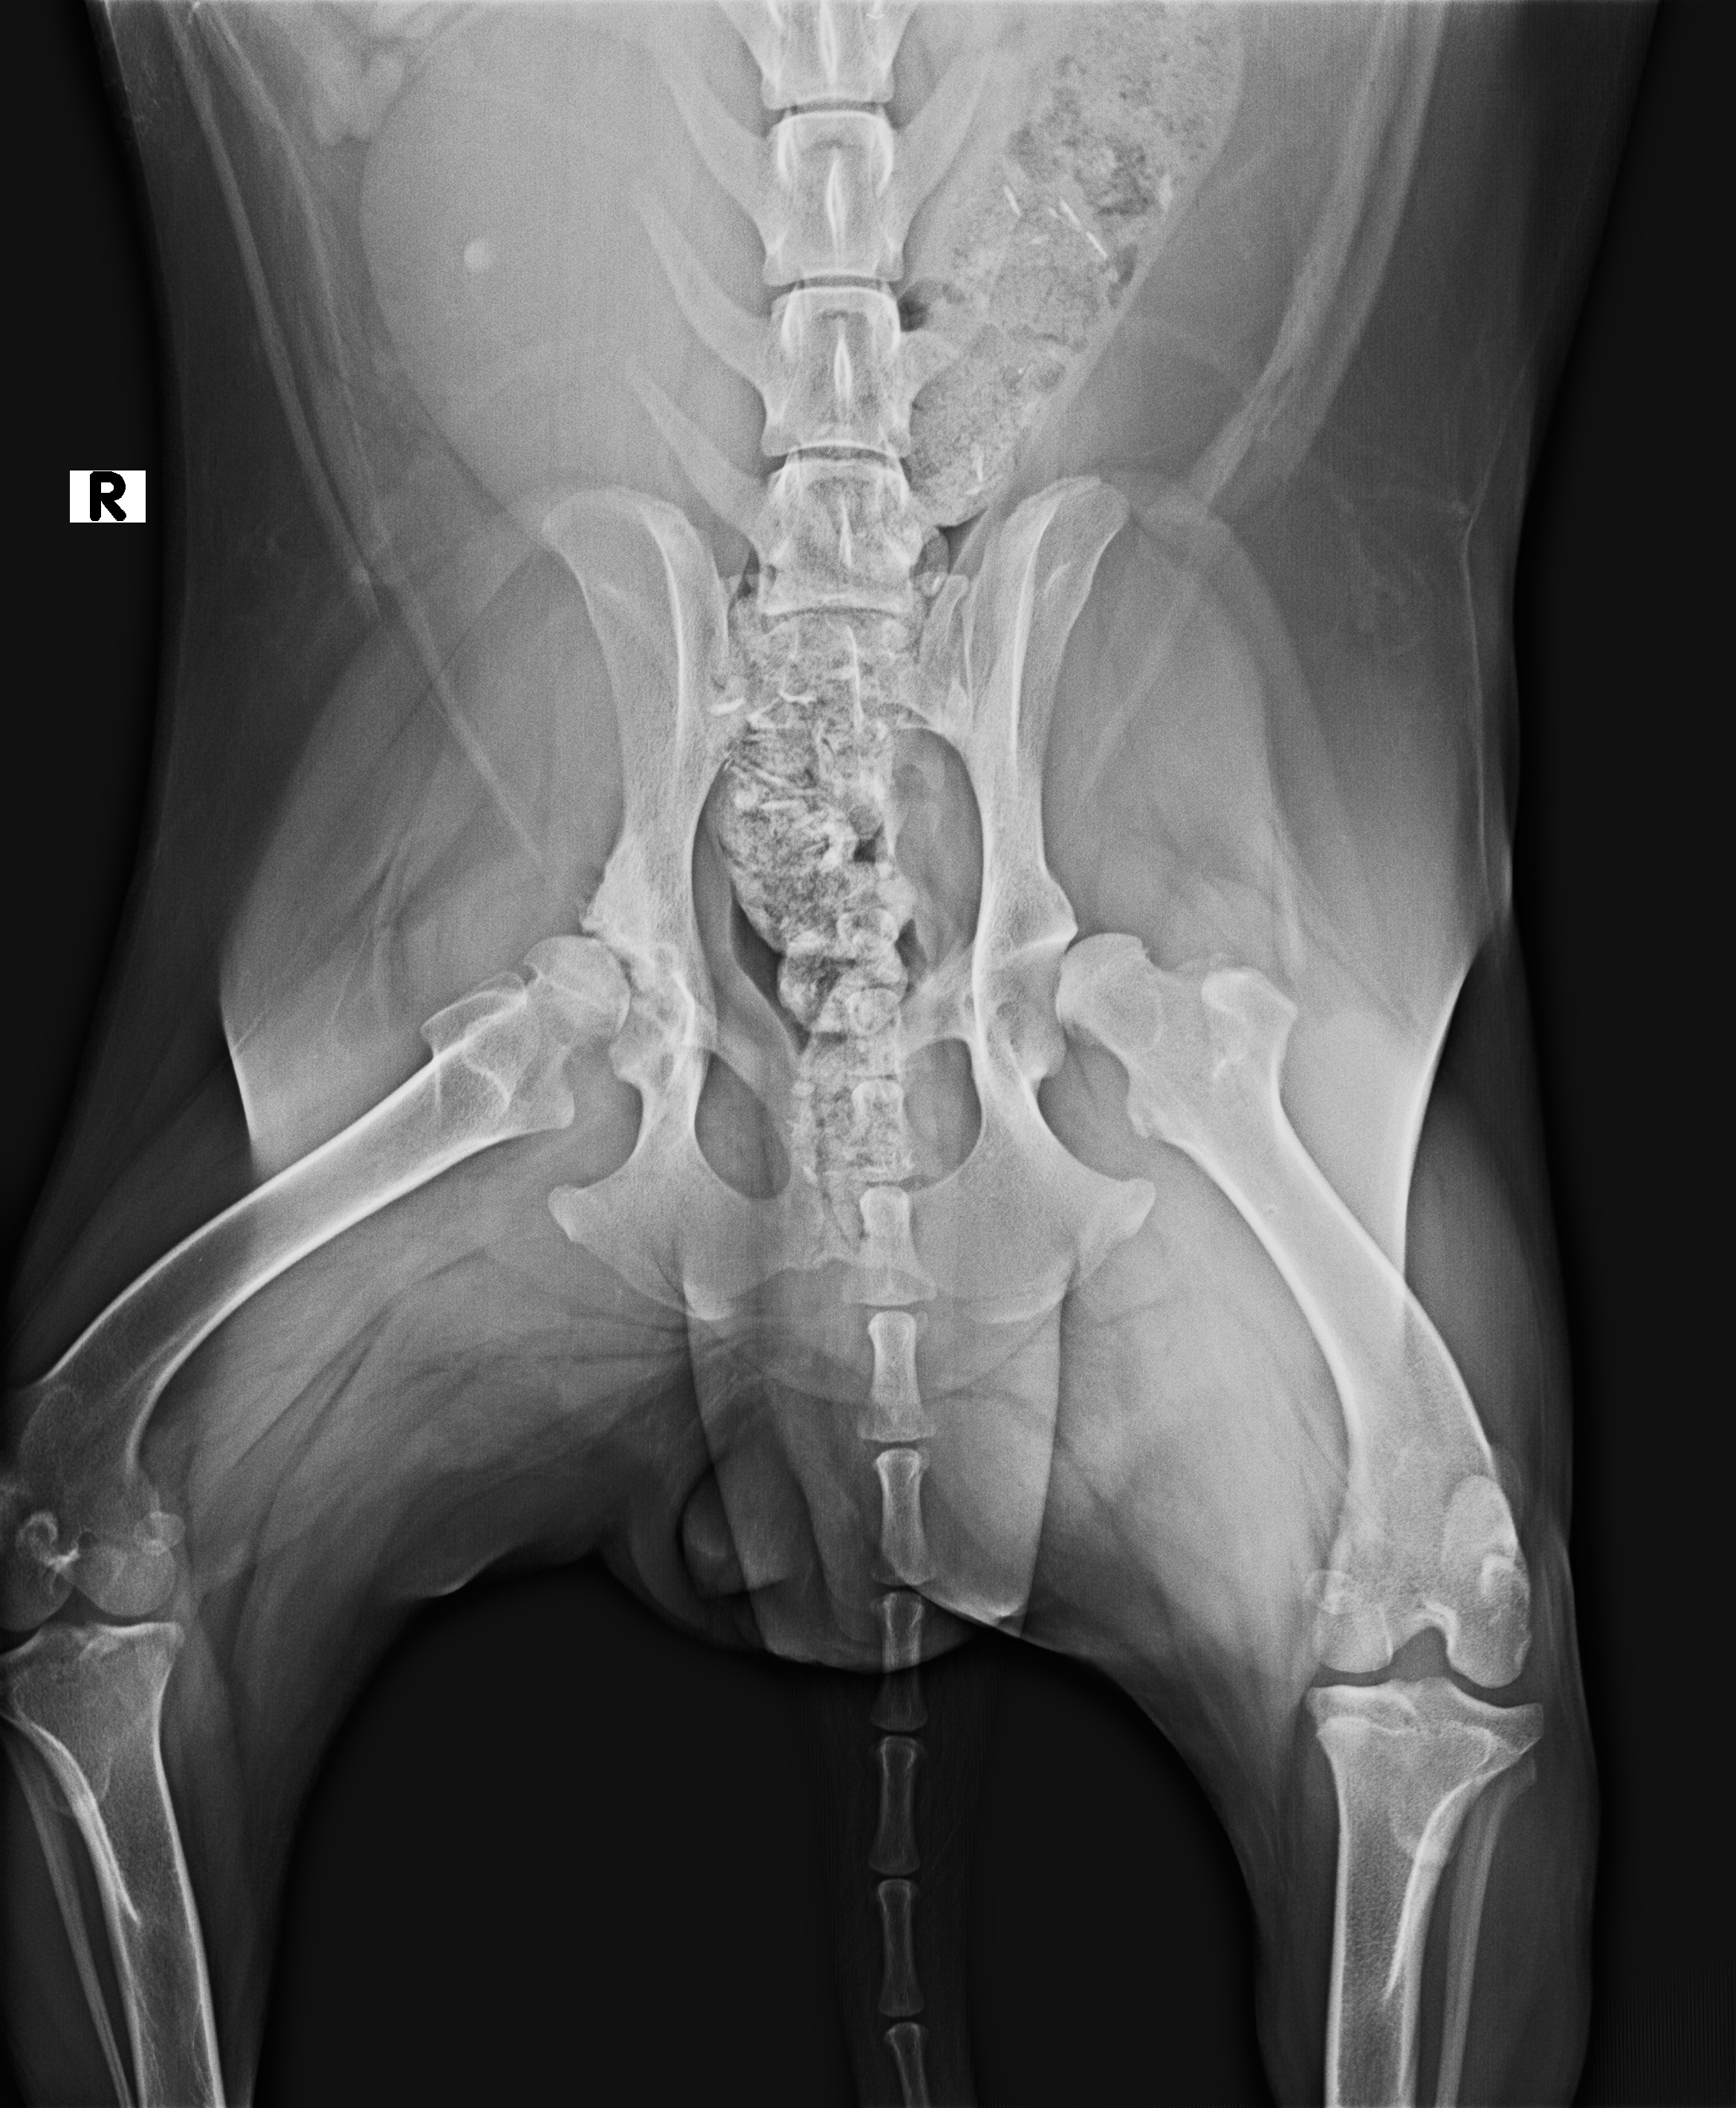

Owner's Complaint : Animal got hit by a lorry near peroorkada junction, bleeding from legs

Purpose of Visit: Treatment | Animal present : YES | Emergency : YES | Accident : YESGeen Indicates normal range | Red indicates abnormal

Images / Radiology

X-RAY

Date | 12-06-2022 | Radiologist | Name of radiologist |

Description Lorem Ipsum is simply dummy text of the printing and typesetting industry. Lorem Ipsum has been the industry's stan |

Observation Lorem Ipsum is simply dummy text of the printing and typesetting industry. Lorem Ipsum has been the industry's stan |